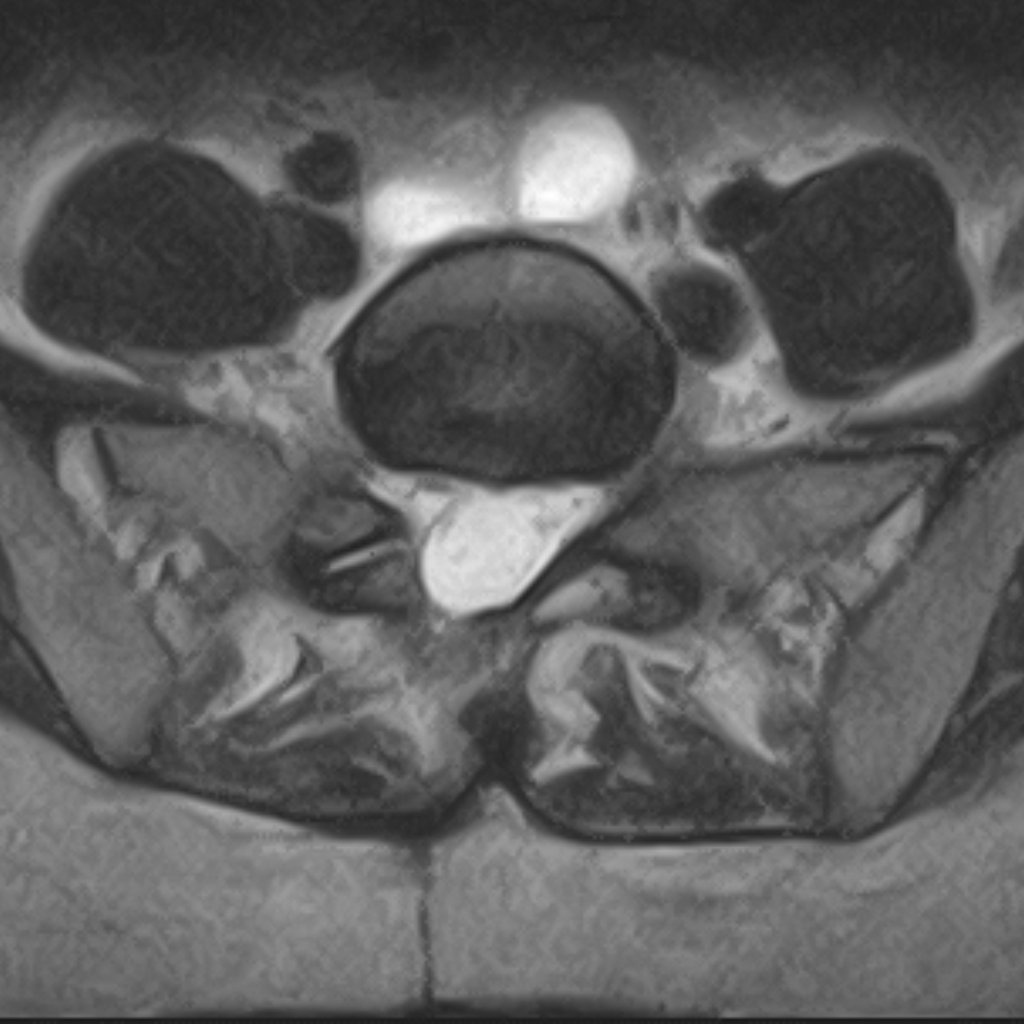

Axiális MRI felvétel — műtét utáni állapot

MRI: műtét utáni állapot — az ideggyök felszabadult a nyomás alól